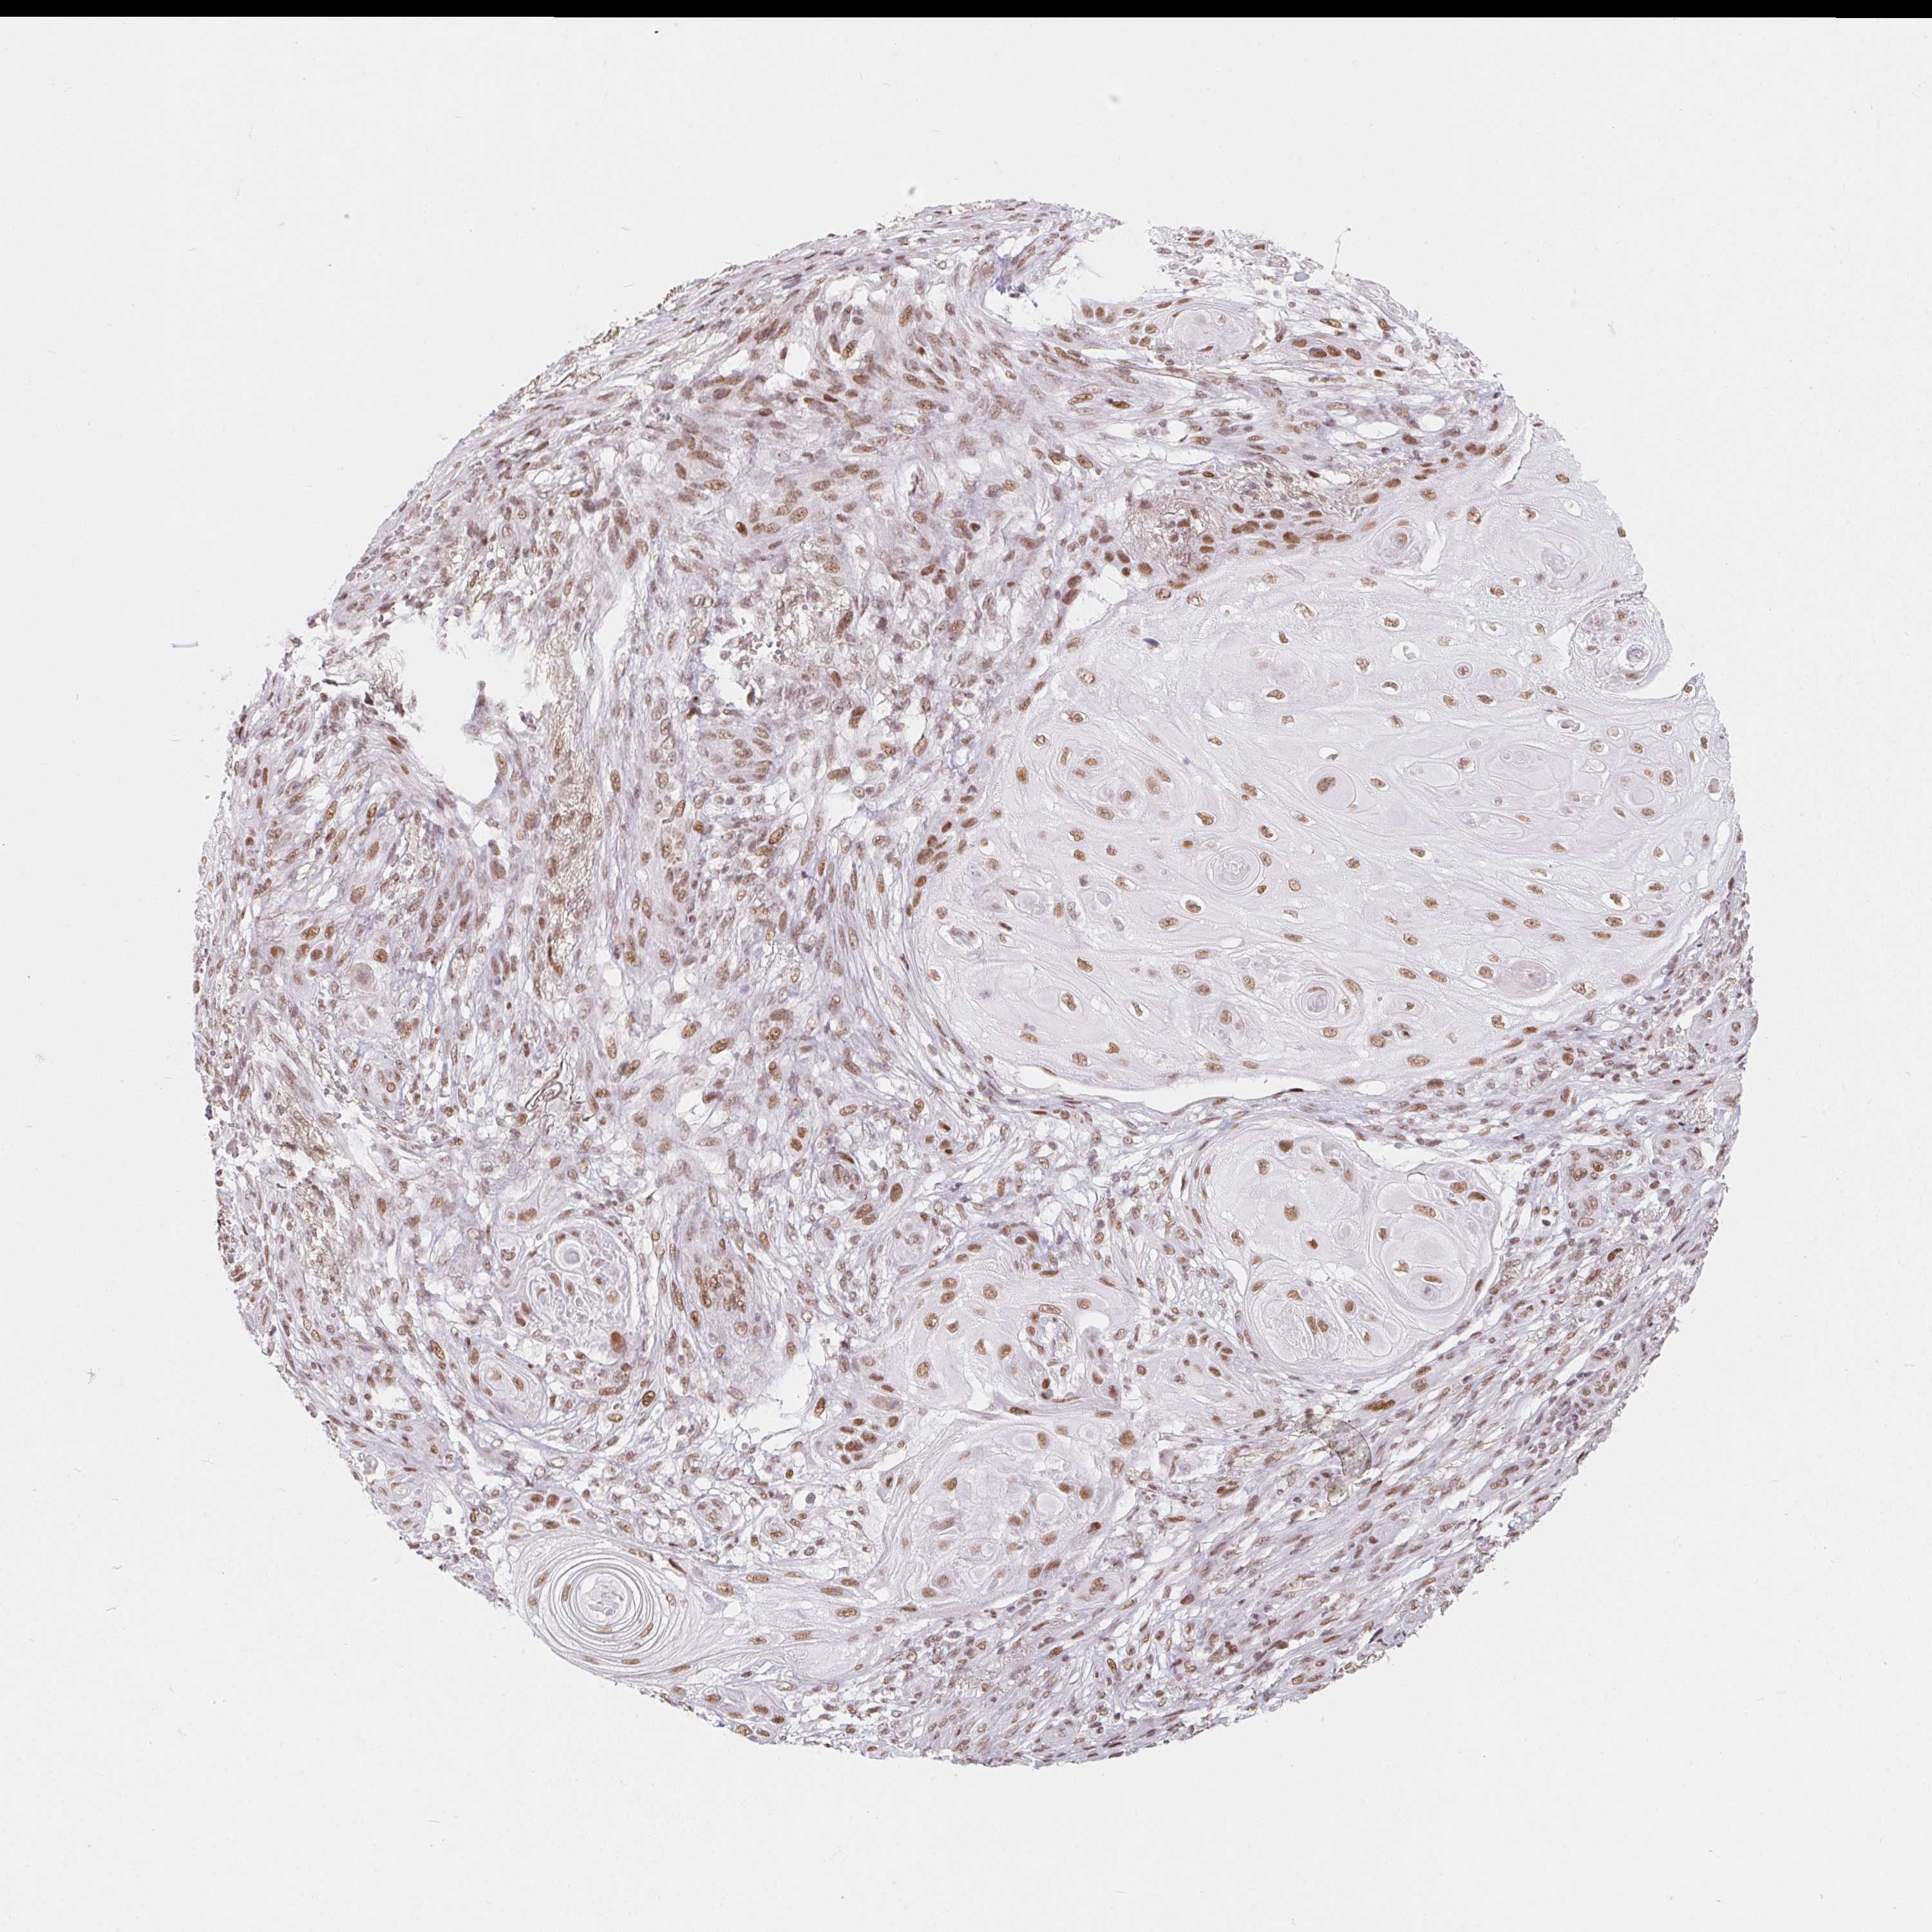

SKIN CANCER - Protein expressioni

A mouse-over function shows sample information and annotation data. Click on an image to view it in a full screen mode. Samples can be filtered based on level of antibody staining by selecting one or several of the following categories: high, medium, low and not detected. The assay and annotation is described here.

Each image is clickable and will lead to virtual microscopy that enables deeper exploration of all samples and also displays staining intensity scores, fraction scores and subcellular localization as well as patient and tissue information for each sample.

Antibody HPA064887

Staining

High

Medium

Low

Not detected

Intensity

Strong

Moderate

Weak

Negative

Quantity

>75%

75%-25%

<25%

None

Location

Nuclear

Cytoplasmic/membranous

Cytoplasmic/membranous,nuclear

Squamous cell carcinoma, NOS